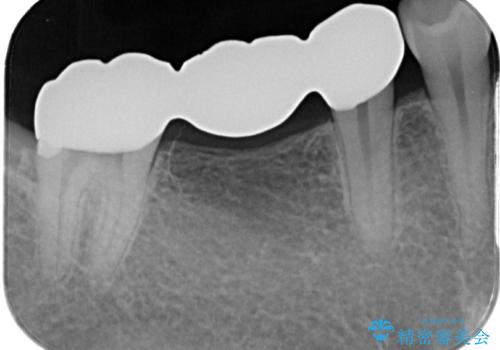

- 以前他院にて、保険診療で治療した金属のブリッジをやり替え希望の患者様です。

金属ブリッジを除去し、虫歯を完全に除去し、形を整え、

精度の高いシリコーン材料にて型どりをしました。

精度の高いブリッジなので、しみるなどの症状もなく経過も良好です。